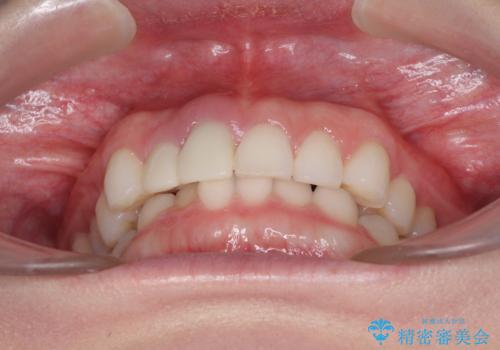

治療前、下顎前歯はほとんど見えない咬み合わせでしたが、矯正治療によりディープバイトが改善されました。